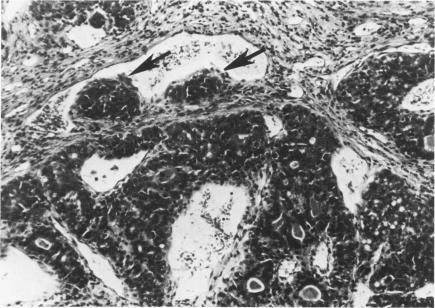

N-乙基-N-亚硝基脲诱导的大鼠乳腺肿瘤的特征

Characterization of N-ethyl-N-nitrosourea--induced mammary tumors in the rat.

A single intraperitoneal inoculation of 180 mg/kg N-ethyl-N-nitrosourea (ENU) into 30-day-old outbred Sprague-Dawley (CD) rats resulted in an 90% incidence of mammary tumors (MTs) after an average latent period of 93 days, with an 85% rate of malignancy. The incidence, induction period, number of tumors per rats, and the rate of malignancy were reduced in rats ovariectomized prior to or shortly after (5 days) ENU exposure. Over 70% of the ENU-induced MTs regressed following ovarioectomy. The malignant MTs developed from nodules located in the terminal end buds (TEB), which are believed to contain the most susceptible cell population for chemical carcinogens. The serum calcium was elevated above control values in 92% of intact rats evaluated with MTs in the absence of bone metastases. No correlation was demonstrated between the volume of MTs or total number of MTs and the serum calcium level. The ENU-induced MT is a reproducible animal model that can be used in the investigation of the early changes in mammary cells (especially TEB) and the interrelationships between the carcinogen and ovarian hormones associated with neoplastic transformation.

摘要